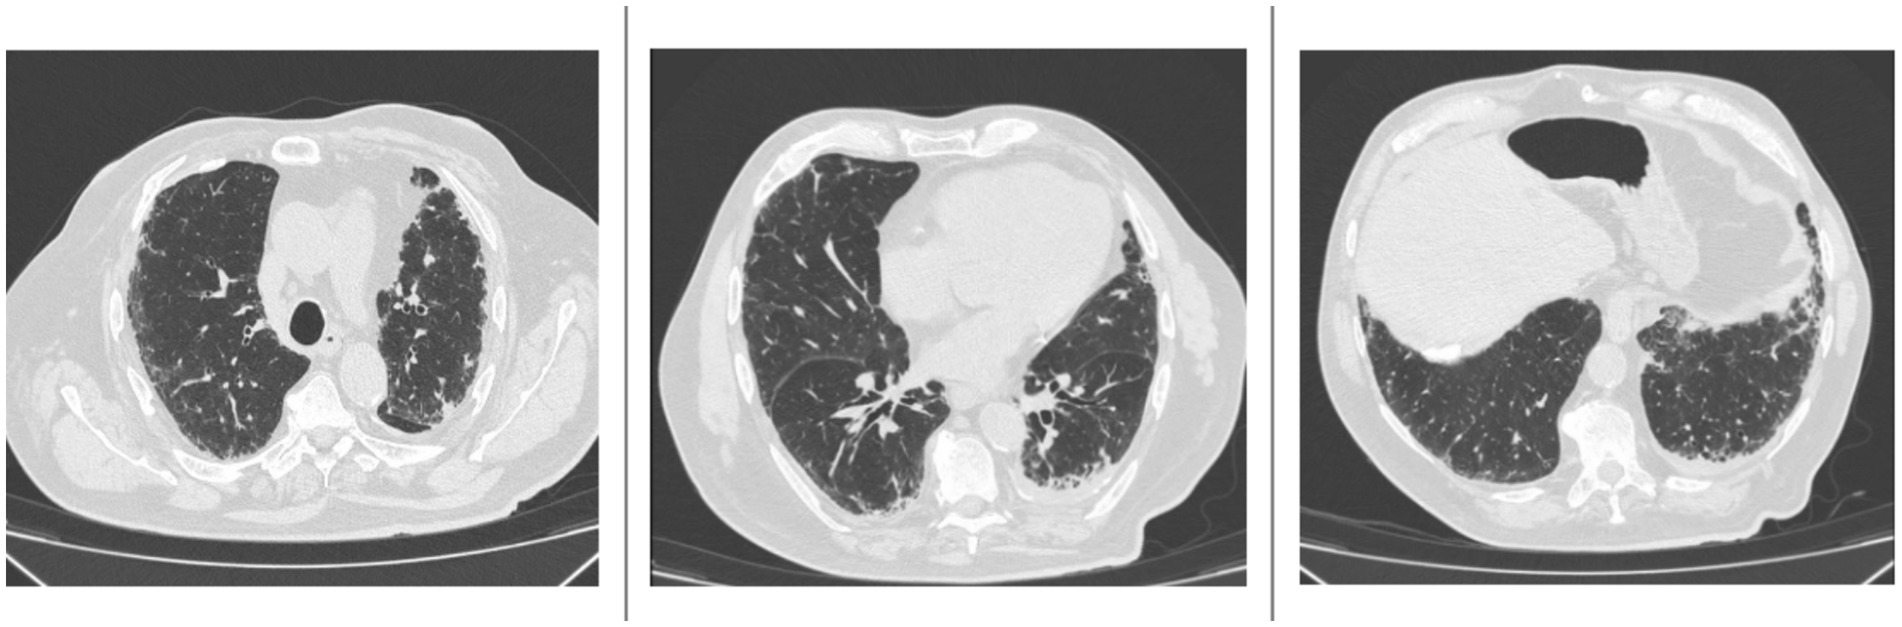

In April 2024, the patient reported subjective worsening of dyspnea. An HRCT was repeated and revealed progression of the interstitial lung fibrosis with radiologic classification of probable usual interstitial pneumonia (UIP) pattern, characterized by the appearance of multiple millimetric submantellar bronchiolectasis, predominantly in both lower lobes, in the lingular lobe, and in the middle lobe, concomitant with finer interstitial reticular thickening, which was also present in the upper lobes (Figure 1).

Figure 1

High-resolution computed tomography (HRCT) scans performed in June 2024 show multiple millimetric subpleural bronchiolectases affecting both lower lobes, the lingula, and the middle lobe. There is also a concomitant diffuse fine interstitial reticular thickening, which is also present in the upper lobes.